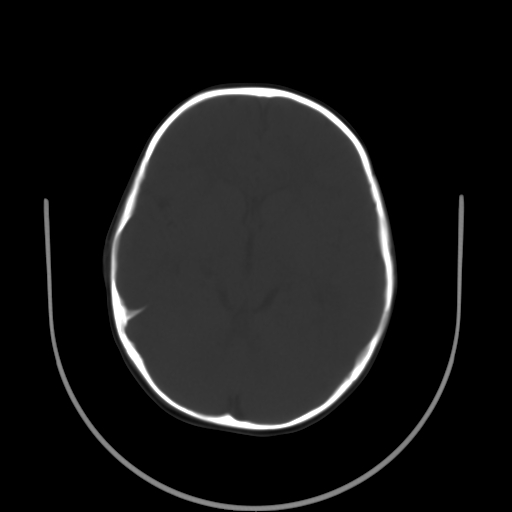

以下是引用拾荒者在2009-10-17 18:38:00的发言:[br]鼻面部皮下积气,右侧睑缘及眼球壁高密度异物影,左侧眼球壁晶状体内侧缘处是圆形低密度影。低密度异物?应提请眼科医生注意。